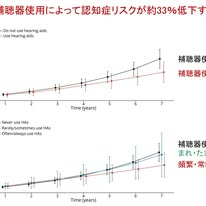

次に2本目は,オーストラリアの研究です.この論文の出発点は,難聴が認知症の重要な危険因子であるという既知の事実です.そこで著者らは,補聴器使用が認知症発症リスクの低下につながるかを検討しました.本研究は単純な観察比較ではなく,target trial emulationと呼ばれる手法が用いています.これは観察データの中で,できるだけランダム化比較試験に近い条件を再現しようとする解析手法です.

対象は70歳以上で中等度の難聴があり,開始時点で認知症がなく,補聴器未使用の人です.補聴器ありが664人,補聴器なしが2113人でした.結果として,全般的な認知機能スコアの推移そのものには大きな差は認められませんでした.しかし,より臨床的に重要な認知症発症リスクでは注目すべき差が示されました.図Aは,補聴器使用あり群となし群で,時間経過に伴う認知症リスクの差が示されていますが, 7年の時点では,補聴器群の認知症リスクが5.0%,非補聴器群が7.5%であり,両群の差が明確になっています.リスク比は0.67(95%CI 0.37~0.97)で,補聴器使用により認知症リスクが約33%低下する可能性が示されました.さらに図Bの使用頻度別解析では,まったく使用しない群の7年時点の認知症リスクが7.3%,まれ・ときどき使用する群が6.8%,頻繁または常時使用する群が4.8%でした.すなわち,補聴器は適切に継続して使用することが重要であることが示唆されます.

ただし,本研究でも因果関係の断定は慎重である必要があります.高度に模倣された解析とはいえランダム化比較試験ではなく,補聴器以外の要因を完全に排除することはできません.また,聴力評価の一部は自己申告に基づいています.それでも,難聴は介入可能な認知症危険因子の一つであり,早期に気づき補聴器による支援を開始することが認知症予防戦略となりうることを示しています.